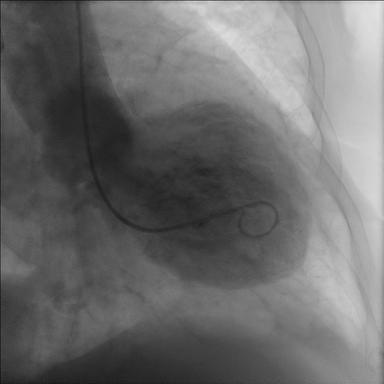

Harmslegill heitir á frummálinu Takotsubo sem er heiti á krabbagildru sem sjá má hér til hliðar við röntgenmyndirnar. Heitið helgast af löguninni sem er sú sama og téðrar gildru

Harmslegill eða Takotsubo er tímabundin afturkræf truflun á samdrætti hjartans sem lýsir sér þannig að hjartað líkist blöðru. Heilkenninu var fyrst lýst árið 1990 í Japan hjá 64 ára gamalli konu sem fékk brjóstverk og var hjartalínuritið með breytingum sem líktust bráðri kransæðastíflu.

Kransæðarnar voru hinsvegar eðlilegar en vinstri slegill dróst óeðlilega saman og gekk samdráttarskerðingin tilbaka á tveimur vikum. Heilkennið var nefnt Takotsubo eftir japanskri kolkrabbagildru því lögun hjartans líktist gildrunni þegar það sló í þessu ástandi. Heilkennið hefur verið kallað ýmsum nöfnum á ensku m.a. broken heart syndrome, stress cardiomyopathy og apical ballooning syndrome en á íslensku hefur það verið nefnt harmslegill.

Dæmigerður harmslegill lýsir sér oftast sem tímabundin afturkræf samdráttarskerðing í broddi og miðhluta vinstri slegils með kröftugum samdrætti í grunnhlutanum. Þó eru til aðrar birtingarmyndir þar sem samdrátturinn getur truflast á mismunandi stöðum í hjartanu og kallast það þá ódæmigerður harmslegill.

Sjúklingur með dæmigerð mynd af harmslegli með samdráttarskerðingu í broddi og miðhluta vinstri slegils með kröftugum samdrætti í grunnhlutanum